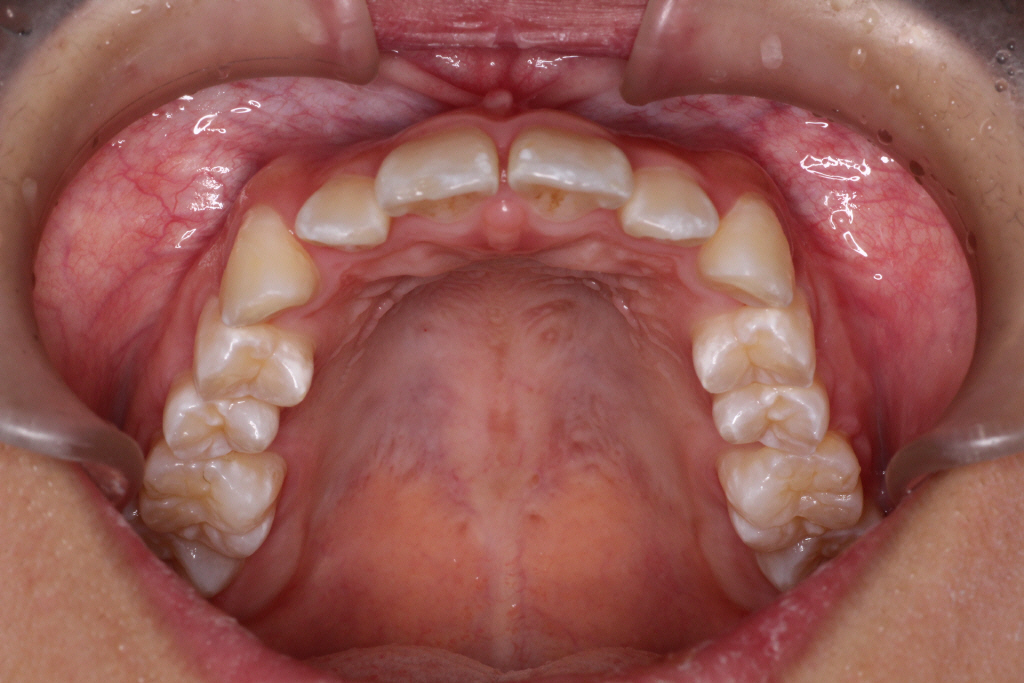

初診時の写真です。

前歯にはがたつき(叢生)がみられ、奥歯は上の歯と下の歯が1歯対1歯で噛んでいることがわかります。

つまり出っ歯の噛み合わせです。

診断:上顎前突・前歯部叢生